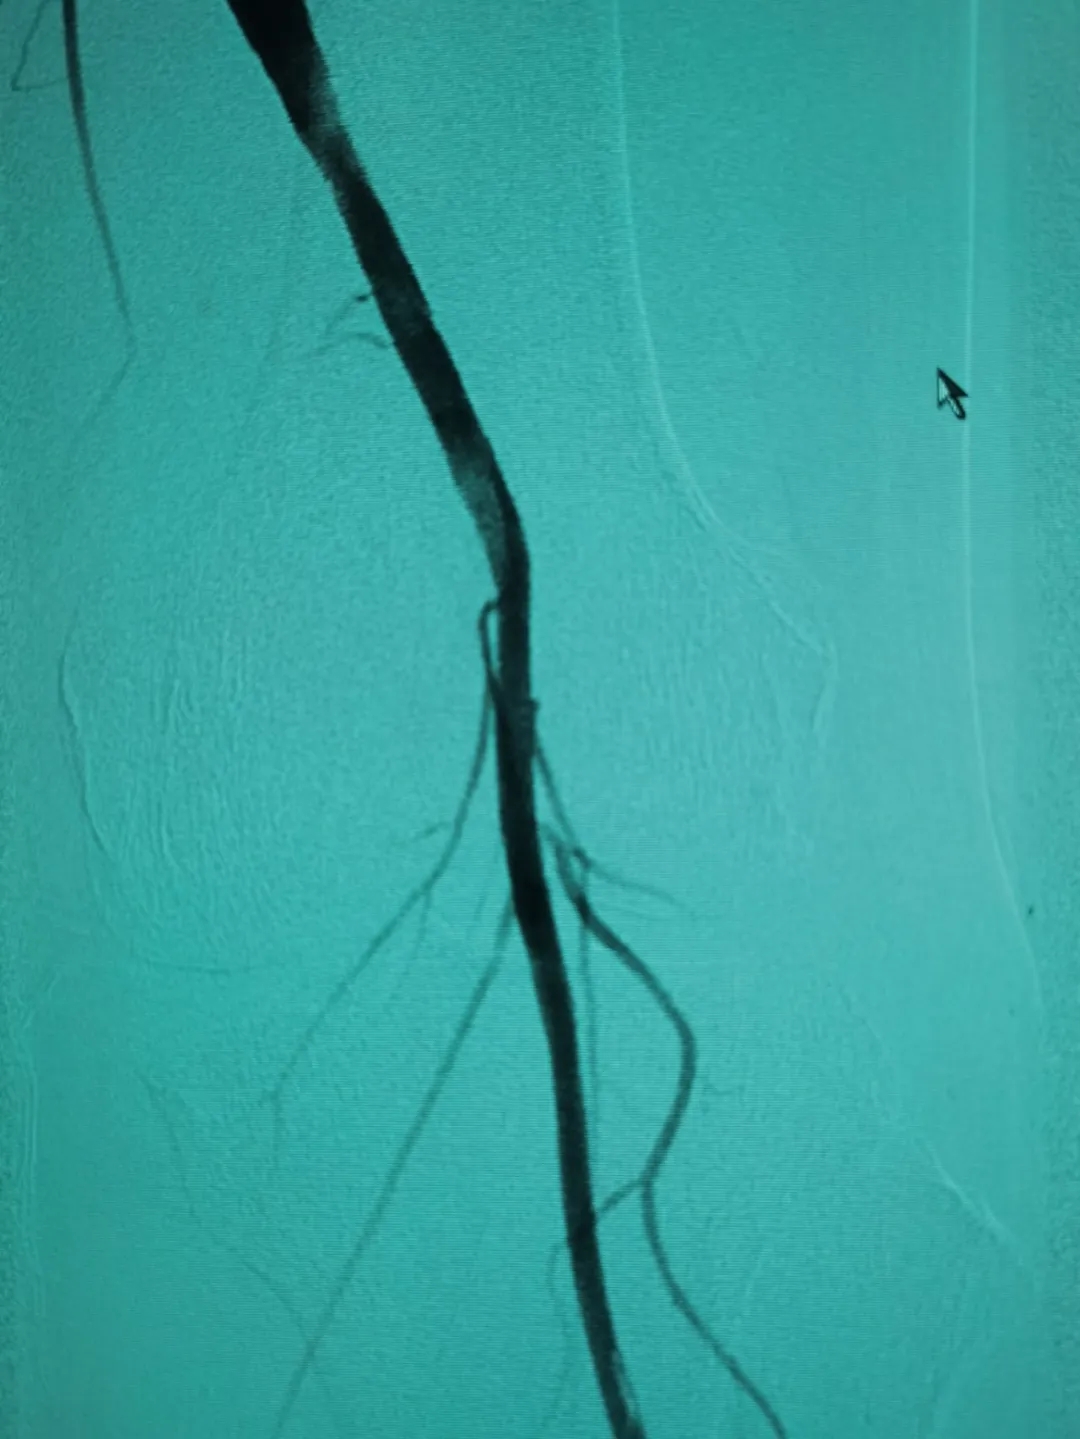

將這些動脈斑塊清除之后,又利用球囊為患者進行血管擴張,病變血管形態(tài)改善良好,可以清楚看到血管內(nèi)大量增生內(nèi)膜被旋切出來,取出遠端保護傘可以看見大量過濾的內(nèi)膜組織。

兩個小時后,手術(shù)成功。術(shù)后周大爺腿疼癥狀即刻消失。據(jù)悉,周大爺現(xiàn)已行走自如,開心地康復(fù)出院啦!